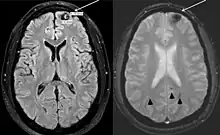

- Lizarraga, Karlo J; De Salles, Antonio AF (20 September 2011). "Multiple cavernous malformations presenting in a patient with Poland syndrome: A case report". Journal of Medical Case Reports. 5 (1): 469. doi:10.1186/1752-1947-5-469. PMC 3195104. PMID 21933407.